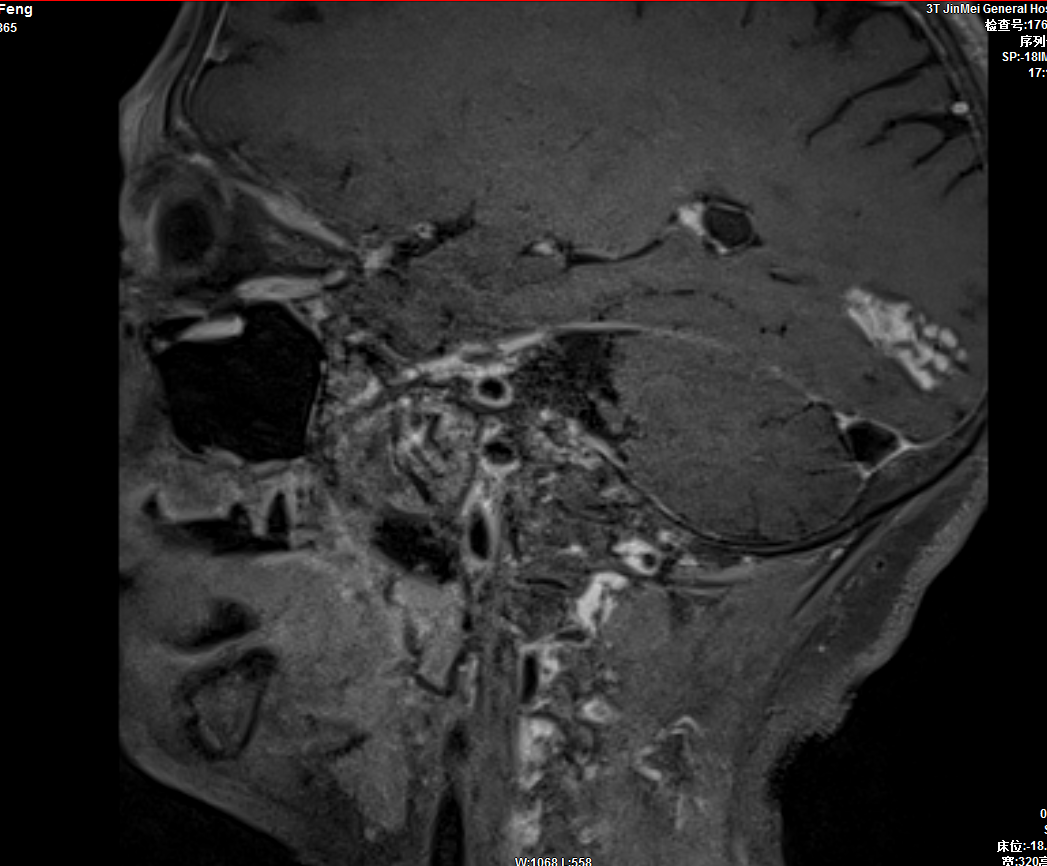

4、頭頸高分辨血管壁成像;

5、是目前公認(rèn)的唯一能夠活體顯示膜迷路積水的影像學(xué)檢查方法,在晉東南地區(qū)率先開(kāi)展,該技術(shù)大大提高了對(duì)膜迷路積水相關(guān)內(nèi)耳疾患的早診率,實(shí)現(xiàn)了精準(zhǔn)診斷、早期干預(yù)、規(guī)范治療。

內(nèi)耳釓造影